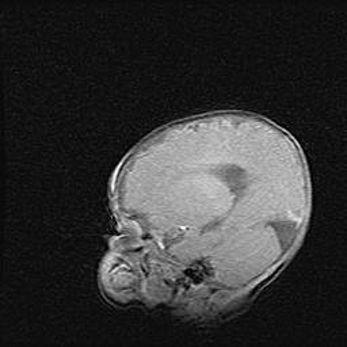

Мальформация Денди-Уокера. Киста задней черепной ямки.

Агенезия мозолистого тела.

Возраст: 2,5 месяца

Вес: 2420 г

Пол: женский

Окружность головы: 37 см

Срок гестации: 32 недели

Мальформация Денди—Уокера — редкий вид патологии ЦНС, представляющий собой врожденный порок развития каудального отдела ствола и червя мозжечка, ведущий к неполному раскрытию срединной (Мажанди) и латеральных (Лушка) апертур IV желудочка мозга. Для этогно синдрома характерна триада симптомов: гипотрофия червя мозжечка и/или полушарий мозжечка, кисты задней черепной ямки, гидроцефалия различной степени. В 70% случаев порок сочетается и с другими аномалиями головного мозга, в частности с агенезией мозолистого тела.